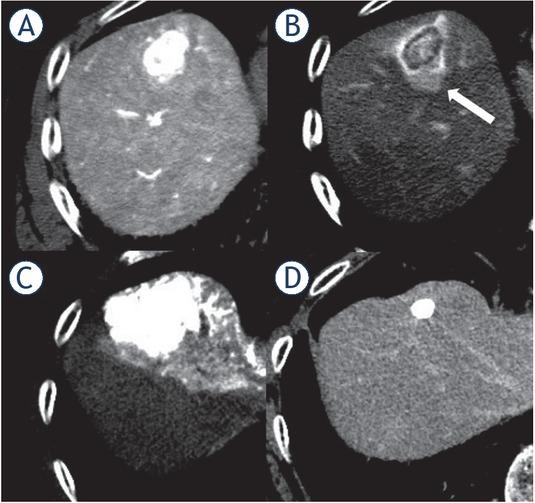

Local tumor recurrence after transcatheter arterial chemoembolization (TACE) in an 82-year-old patient with a hepatocellular carcinoma. (A) Early-phase computed tomography during hepatic arteriography (CTHA) demonstrated a hypervascular nodule in S5. (B) Late-phase CTHA demonstrated the corona enhancement around the tumor (white arrow). (C) Non-contrast-enhanced computed tomography performed immediately after TACE showed dense accumulation of iodized oil throughout the tumor, but not in the entire corona enhancement area. (D) In contrast enhanced magnetic resonance images obtained 4 months after TACE, local recurrence developed around the tumor (black arrow).